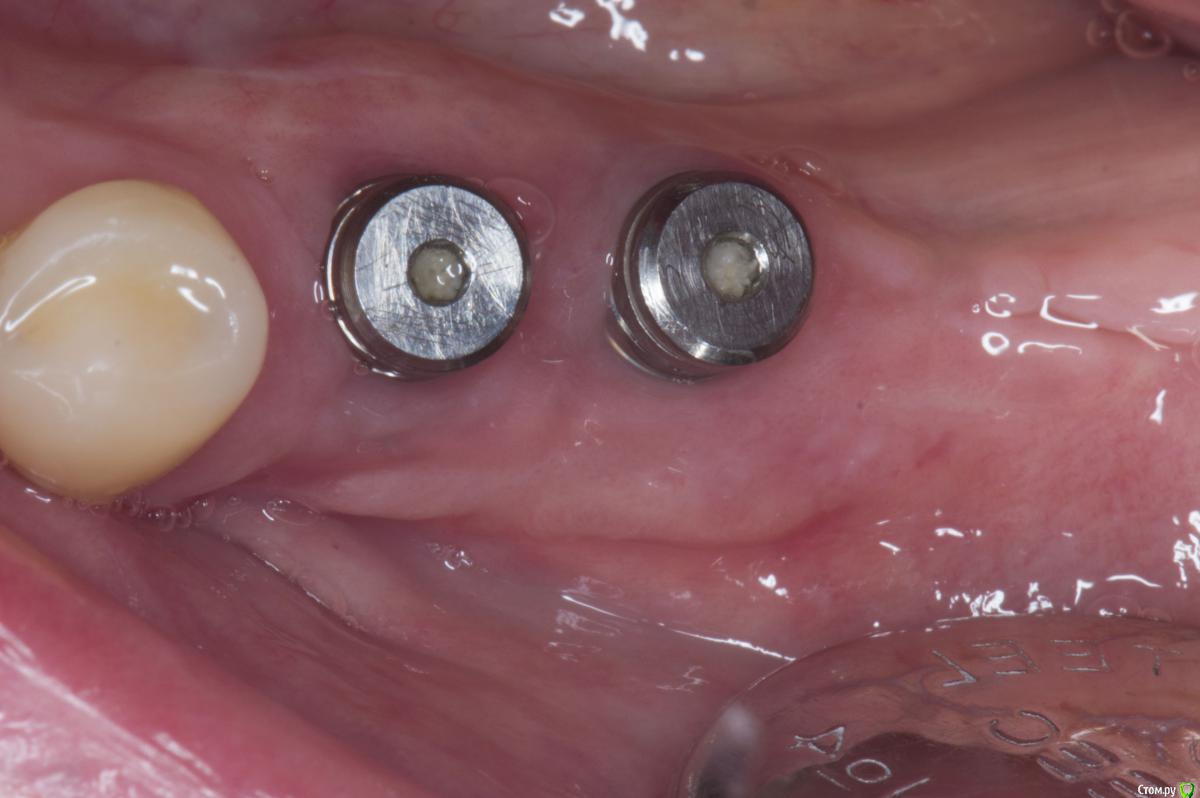

Sampson Опубликовано 7 августа, 2018 Автор Поделиться Опубликовано 7 августа, 2018 месяц спустя Ссылка на комментарий